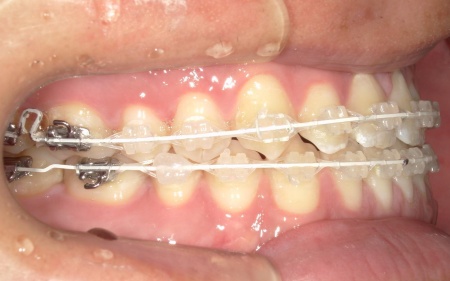

②白色(セラミック)のブラケットとホワイトワイヤーを用いたセラミックブラケット矯正

矯正の方法は①と同様ですが、装置の色味が異なります。

メリット:装置が白いため歯の色に馴染みやすく、目立ちにくい

デメリット:色の濃い飲食物で、装置が変色するおそれがある

患者様は「できるだけ目立ちにくい装置を使用したい」とのことから、②のセラミックブラケット矯正を選択されました。

まず、下奥歯(臼歯)を歯茎の外側に持ち上げる「挺出(ていしゅつ)」という処置を行いました。

奥歯が少し高くなることで、下顎全体がわずかに後ろへ動くため、前歯の噛み合わせが整いやすくなります。

加えて、上下の前歯には「IPR」という処置を行いました。これは、歯の表面のエナメル質をごくわずかに削り、歯を動かすためのスペースを作る方法です。

このスペースを利用して前歯を後方へ移動させ、審美性の改善を目指しました。